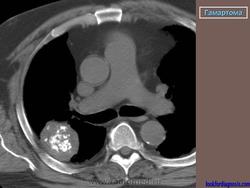

Гамартома

Приложения:

1.gam_.6_250.jpg2.gam_.9_116.jpg3.gam_.10_100.jpg1.gam_.7_169.jpg2.gam_.8_149.jpg